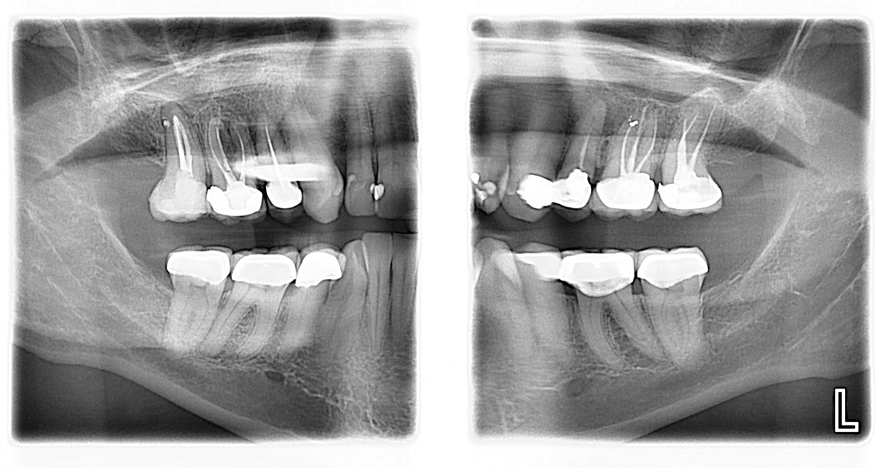

A 56-year-old female patient required an extensive treatment plan, including multiple crowns and fillings in each quadrant. She was able to complete treatment only in stages. By the time one quadrant was completed, she began to have pain on the mesial of tooth No. 20 (Figure 1 and Figure 2). Because the patient had no more dental benefits for the year, she needed to alleviate the sensitivity and prevent further problems between appointments. The doctor recommended SDF to stave off the sensitivity she was experiencing and to prevent growth of the lesion. Silver diamine fluoride was placed during a restorative appointment, and her sensitivity and pain subsided. When she returned a month later for her hygiene visit, she stated her pain had returned. A second SDF treatment was administered, which prevented the pain from returning a third time, until her restorative treatment could resume.

(2.) Patient required an extensive treatment plan, including multiple crowns and fillings in each quadrant.

Figure 2